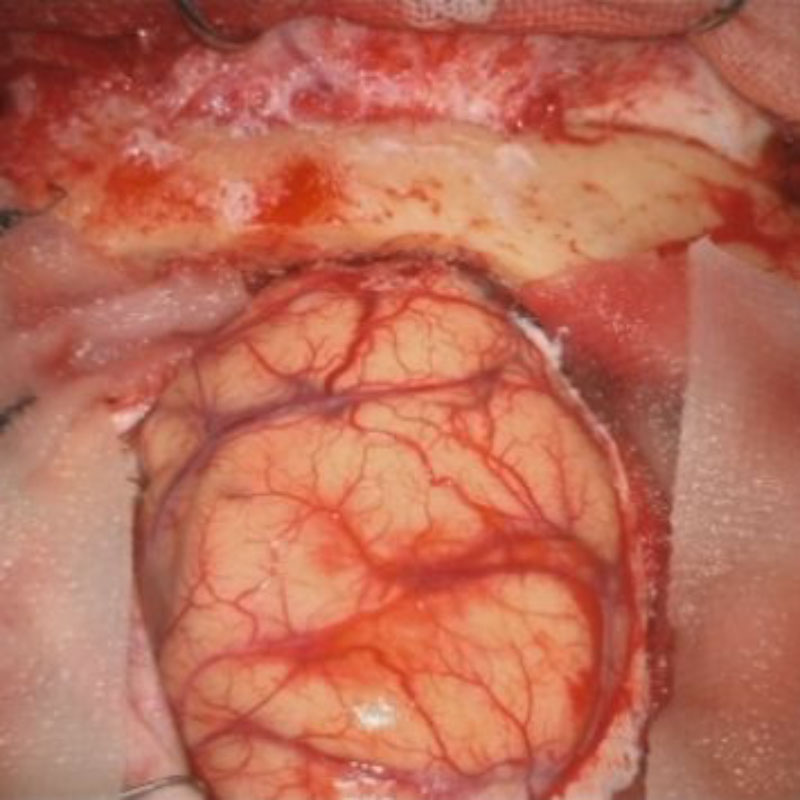

頭蓋咽頭腫

頭蓋内腫瘍摘出術

No.’25_96 手術前1

No.’25_96 手術前2

No.’25_96 摘出 前

No.’25_96  摘出 中

No.’25_96 摘出 後